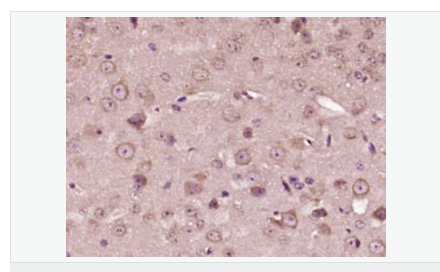

| 產(chǎn)品應(yīng)用 | ELISA=1:5000-10000 IHC-P=1:100-500 IHC-F=1:100-500 IF=1:200-800 (石蠟切片需做抗原修復) not yet tested in other applications. optimal dilutions/concentrations should be determined by the end user. |

| 產(chǎn)品介紹 | This gene encodes a member of the corticotropin-releasing factor family. The encoded preproprotein is proteolytically processed to generate the mature neuropeptide hormone. In response to stress, this hormone is secreted by the paraventricular nucleus (PVN) of the hypothalamus, binds to corticotropin releasing hormone receptors and stimulates the release of adrenocorticotropic hormone from the pituitary gland. Marked reduction in this protein has been observed in association with Alzheimer's disease. Autosomal recessive hypothalamic corticotropin deficiency has multiple and potentially fatal metabolic consequences including hypoglycemia and hepatitis. In addition to production in the hypothalamus, this protein is also synthesized in peripheral tissues, such as T lymphocytes, and is highly expressed in the placenta. In the placenta it is a marker that determines the length of gestation and the timing of parturition and delivery. A rapid increase in circulating levels of the hormone occurs at the onset of parturition, suggesting that, in addition to its metabolic functions, this protein may act as a trigger for parturition. [provided by RefSeq, Nov 2015] Function: This hormone from hypothalamus regulates the release of corticotropin from pituitary gland. Subunit: Interacts (via C-terminus) with CRFR1 (via N-terminal extracellular domain). Subcellular Location: Secreted. Similarity: Belongs to the sauvagine/corticotropin-releasing factor/urotensin I family. SWISS: P06850 Gene ID: 1392 Database links: Entrez Gene: 1392 Human Entrez Gene: 12918 Mouse Omim: 122560 Human SwissProt: P06850 Human SwissProt: Q8CIT0 Mouse Unigene: 75294 Human Unigene: 290689 Mouse Unigene: 10349 Rat Important Note: This product as supplied is intended for research use only, not for use in human, therapeutic or diagnostic applications. CRF陽性神經(jīng)元的胞體廣泛分布于下丘腦的室旁核、背縫核和藍斑核,這些區(qū)域也是去甲腎上腺素(NE)神經(jīng)元與5-羥色胺(5-HT)神經(jīng)元密集的區(qū)域。 CRF既具有神經(jīng)遞質(zhì)的性質(zhì)又具有神經(jīng)激素的性質(zhì)。CRF是聯(lián)系神經(jīng)系統(tǒng)與內(nèi)分泌系統(tǒng)的橋梁,在情感障礙疾患如焦慮和抑郁的發(fā)病中發(fā)揮重要作用. |